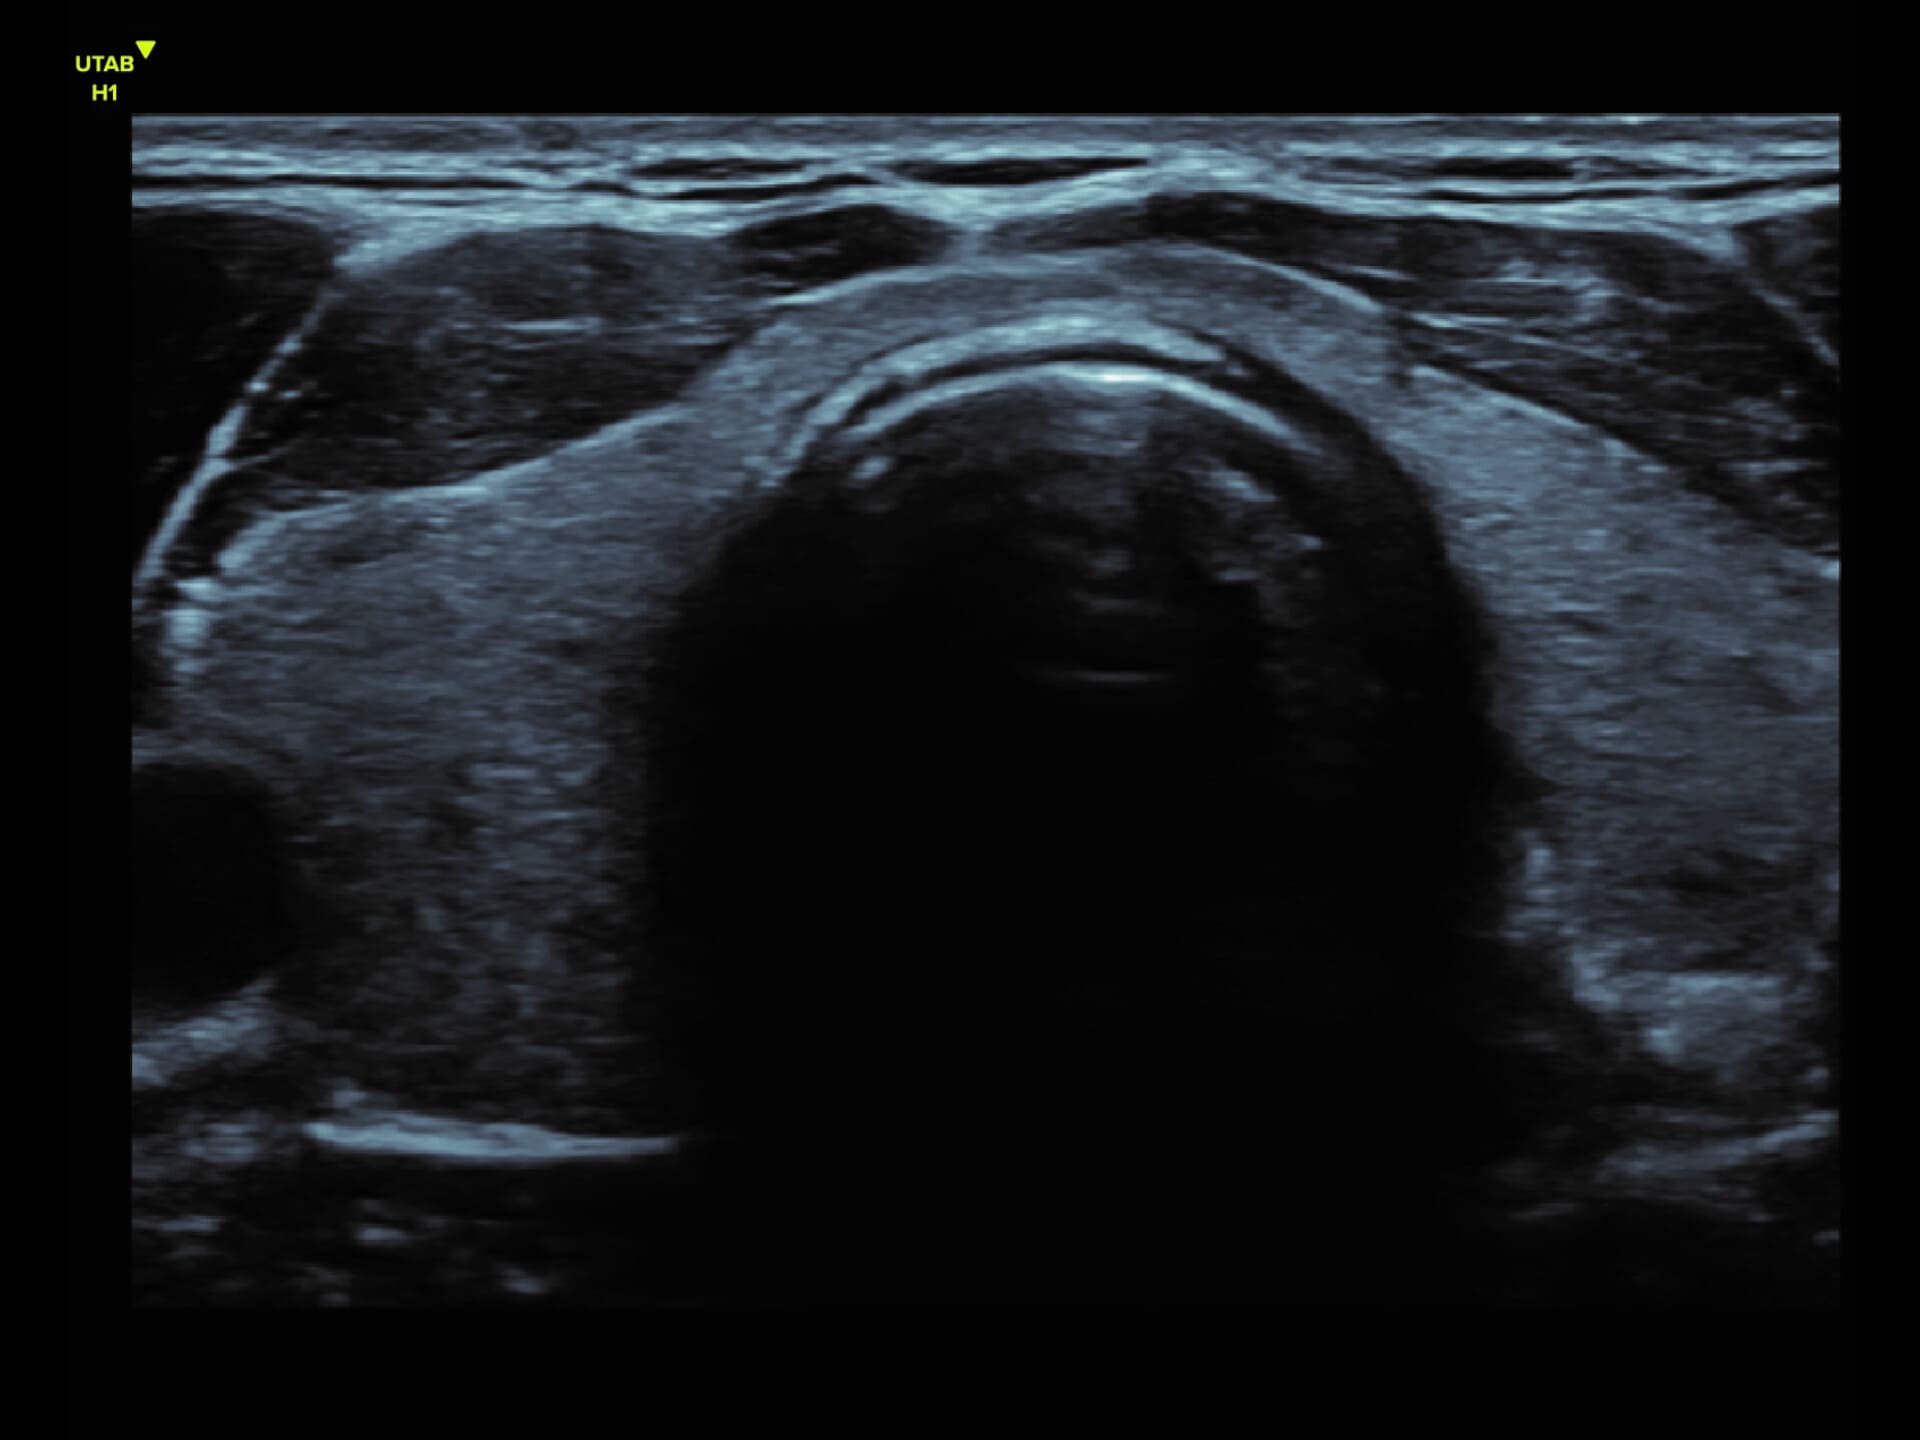

L9-2 Linear Array Probe

Precision at the Surface

Crystal-clear imaging for muscles, vessels, and soft tissues—perfect for targeted exams and real-time procedures.

The L9 – 2 is a linear array ultrasound probe featuring advanced wideband technology, which enables a broader frequency range for superior image resolution and clarity. This enhanced imaging capability makes it ideal for a range of clinical applications.

About L9-2

The L9 – 2 is a linear array ultrasound probe featuring advanced wideband technology, which enables a broader frequency range for superior image resolution and clarity.

This enhanced imaging capability makes it ideal for a range of clinical applications.

L9 - 2 Linear Array Probe

2 - 10 MHz

DLP

192 elements

Applications:

Musculoskeletal, Thyroid, Small Parts, Pediatrics, Peripheral Vascular, Breast, Obstetrics

B-mode, HI, XBeam, Speckle Reduction, Virtual Convex, M-mode, PW (Update, Duplex, Triplex, HPRF), CFM, PD

7 x 43 mm